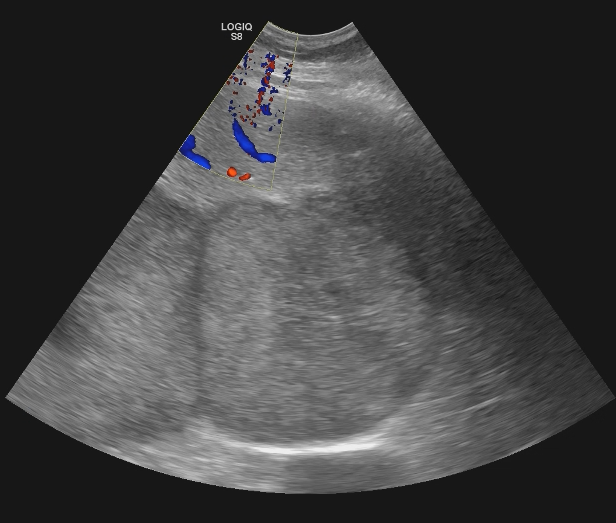

Descripción de los hallazgos ecográficos y las imágenes más relevantes para la resolución del caso

Se realiza ecografía abdominal en la consulta que muestra abundantes lesiones ocupantes de espacio en ambos lóbulos hepáticos, alguna de gran tamaño.Otras pruebas complementarias realizadas (si existen)

Hígado con múltiples metástasis y ambos lóbulos, la más gruesa de uns 10,2 cm en los segmentos VI y VII. Colecistolitiasis. Vía biliar no dilatada.Esplenomegalia con nódulos 12 y 14 mm inespecíficos. Nódulos suprarrenal izquierdo de 46 mm y dos derechos de 14 y 18 mm, inespecificos. Páncreas de medida y morfología normal. No hay signos de uropatía obstructiva. Riñones dentro de la normalidad con el nefrograma simétrico. Adenopatías retroperitoneales de predominio retrocavales y enteraortocava, la mas gruesa de 19 mm. Lesiones líticas en las costillas, esternón, vertrebrales y pelvianas. Conclusión: Enfemerdad neoplasia con diseminacion pulmonar y hepática, osea, ganglionar y probablemente esplenica y suprarrenal bilateral. No se identifica origen.

Biopsia de nódulo hepático positiva para melanoma maligno.